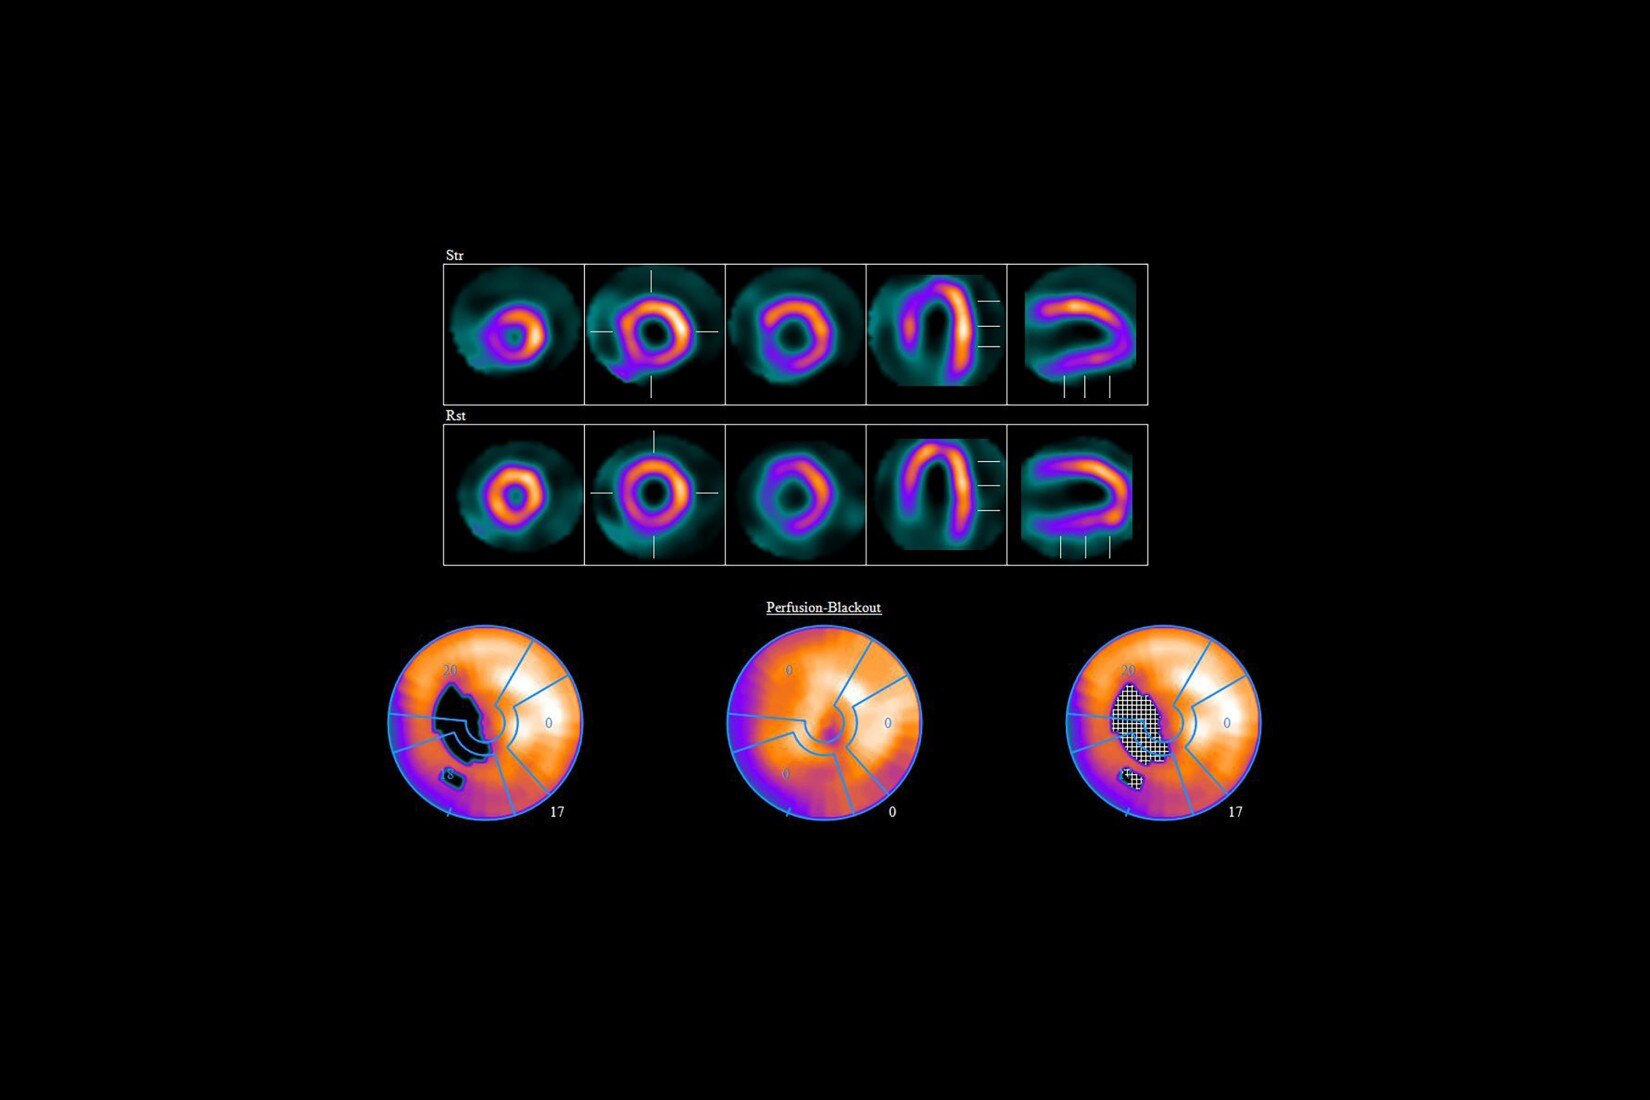

Discover the advanced capabilities of the SIGNA™ Architect, GE HealthCare's 3T magnet MRI system. Featuring a 128-channel Total Digital Imaging (TDI) receive chain and exceptional 44mT/m @ 200T/m/s gradient performance, this system sets a high standard for precision. Streamline your workflow effortlessly with products like AIR™ Recon DL, AIR™ Coils, and Sonic DL™, designed to enhance your diagnostic efficiency.

Clinical confidence

Reinforce your clinical confidence with the SIGNA™ Architect's AI-based applications, powered by Edison. Implement feet-first imaging for all exams, emphasizing a patient-friendly approach. The Effortless AIR™ Recon DL further enhances imaging efficiency, providing diagnostic precision to meet your high standards.